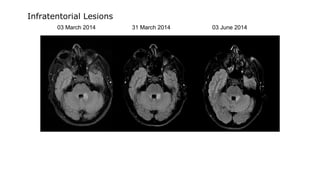

03 March 2014 31 March 2014 03 June 2014

Infratentorial Lesions

31 March 2014 Gadolinium enhancement of symptomatic lesion